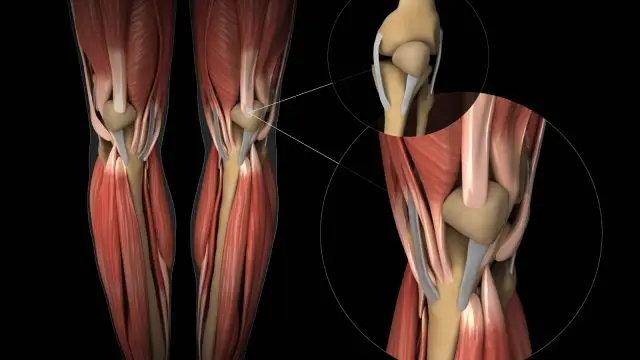

Stres kırığı, aslında tam olarak bir kırık değildir. Ayağın yük taşıması sırasında her bölgenin farklı işlevleri vardır. Yürüyüş esnasında ayağın her bölgesi belli miktarda yük taşır. Ancak ayağın anatomik yapısı zorlanırsa ve yanlış yerlere fazla miktarda yük bindirilirse kemiğin basınç altında kalmasına sebep olunur. Basınç ise tarak ve kaval kemiklerinde ödeme neden olur. Ödem geliştikçe kemiğin içerisindeki basıncı arttırır. Bu basınç ise hastaya ağrı olarak yansır.

Stres kırığı daha çok alt baldır kemikleri ve ayak tarak kemiklerinde meydana gelir. Bunun sonucunda ise küçük çatlaklar meydana gelir. Araştırmalar sonucu stres kırığının daha çok enerji gerektiren sporları yapan kişilerde oluştuğu görülmüştür. Bu enerji gerektiren sporlar ise basketbol, tenis, atletizm gibi sporlardır. Çünkü bu sporlarda zemine ayak çarpma hareketi daha çok yapılır. Stres kırığı ayrıca saha ve pist sporları ile uğraşanlarda da görülebilir.